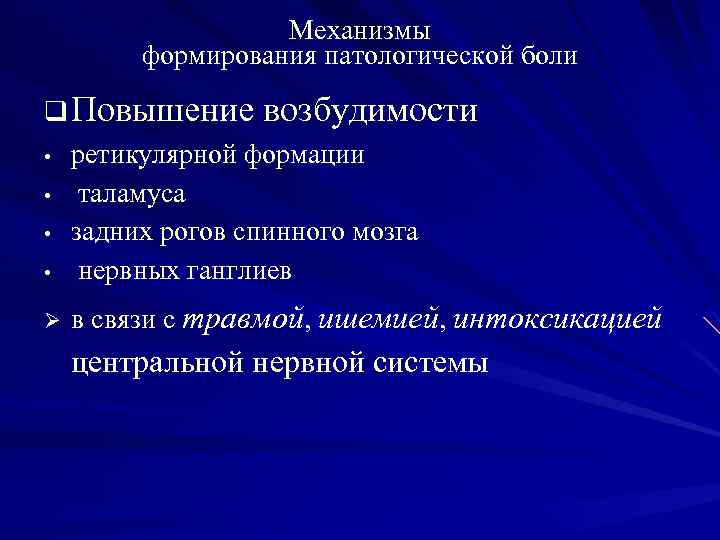

Диплопия: механизм развития и методы лечения